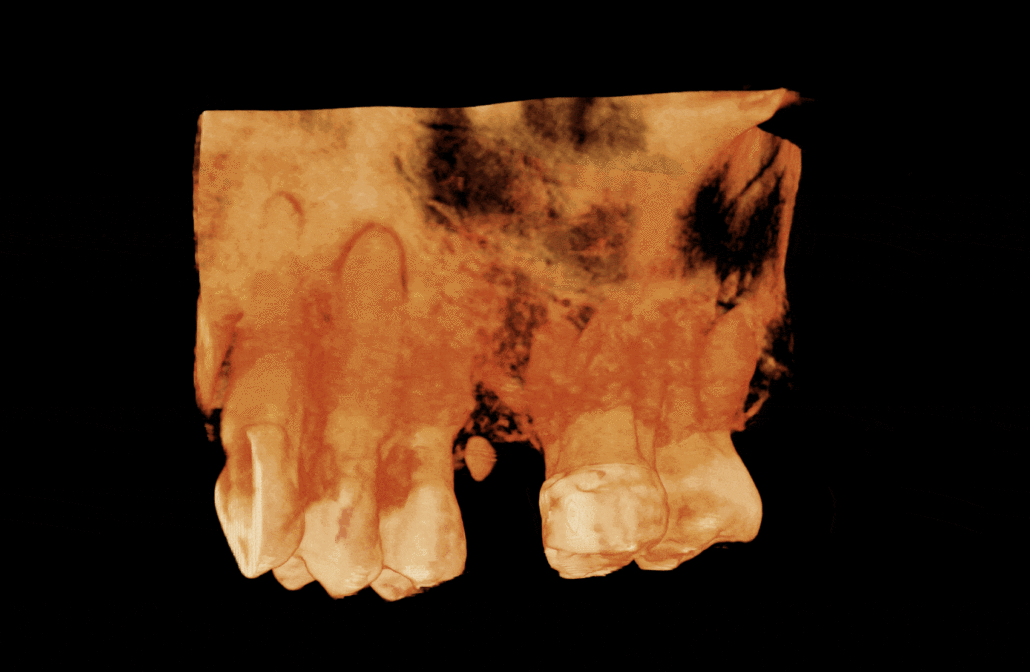

Region UL3-UL8 is imaged. The UL6 is absent. “Pillow”-like mucosal swellings on the floor and walls of the left maxillary sinus, indicating polypoidal mucosal thickening. This appearance is consistent with chronic rhinosinusitis. The apices of the UL7 and UL8 have an intimate relationship with the antral floor and the Schneiderian membrane.

The roots of the UL3/4/5 demonstrate hypercementosis. Image 1

The UL4 has two roots which are practically fused due to hypercementosis. The buccal root is straight. The palatal root has a slight buccal curve. The apical half of both roots is not visible (possibly obliterated). Image 2

The UL5 has two roots which are practically fused due to hypercementosis. The apical half of the buccal root is not visible (possibly obliterated). Image 3